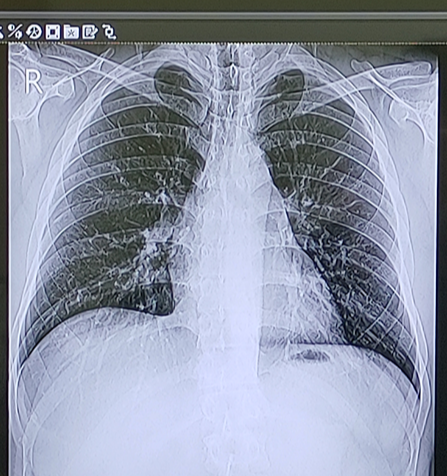

의사께서 X-Ray를 찍어보자고 하셨다.

내과에서 X-Ray라니 굉장히 특이하다고 생각했다.

의료 분야에 대해서는 까막눈이었기 때문에 뭐가 문젠지 몰랐는데,

근처 의료인에게 물어보니 원래 폐는 투명하게 나와야 하는데

흰색 선이 보이지 않느냐, 전부 염증이다 라는 설명을 들을 수 있었다.

그렇다. 나는 코로나 후유증으로 기관지염을 앓게 된 것이었다.